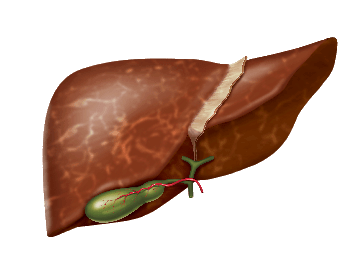

Найбільш важливі функції печінки пов'язані з

роботою гепатоцитів - клітин печінки:

- метаболічна участь в обміні білків, жирів, вуглеводів, вітамінів, мікроелементів, гормонів

- захисна руйнування біологічно активних агентів

- знешкоджує знешкодження токсичних речовин

- секреторна екзокринна - утворення і виділення жовчі, ендокринна - виділення в кров синтезованих або метаболізованих продуктів

Як відбувається пошкодження гепатоцитів?

В основі пошкодження гепатоцитів лежить запалення, яке може привести до загибелі клітин печінки (цитолизу)

Як розвивається процес руйнування печінки?

Основні стадії розвитку

захворювань печінки

Основні стадії

розвитку захворювань

печінки